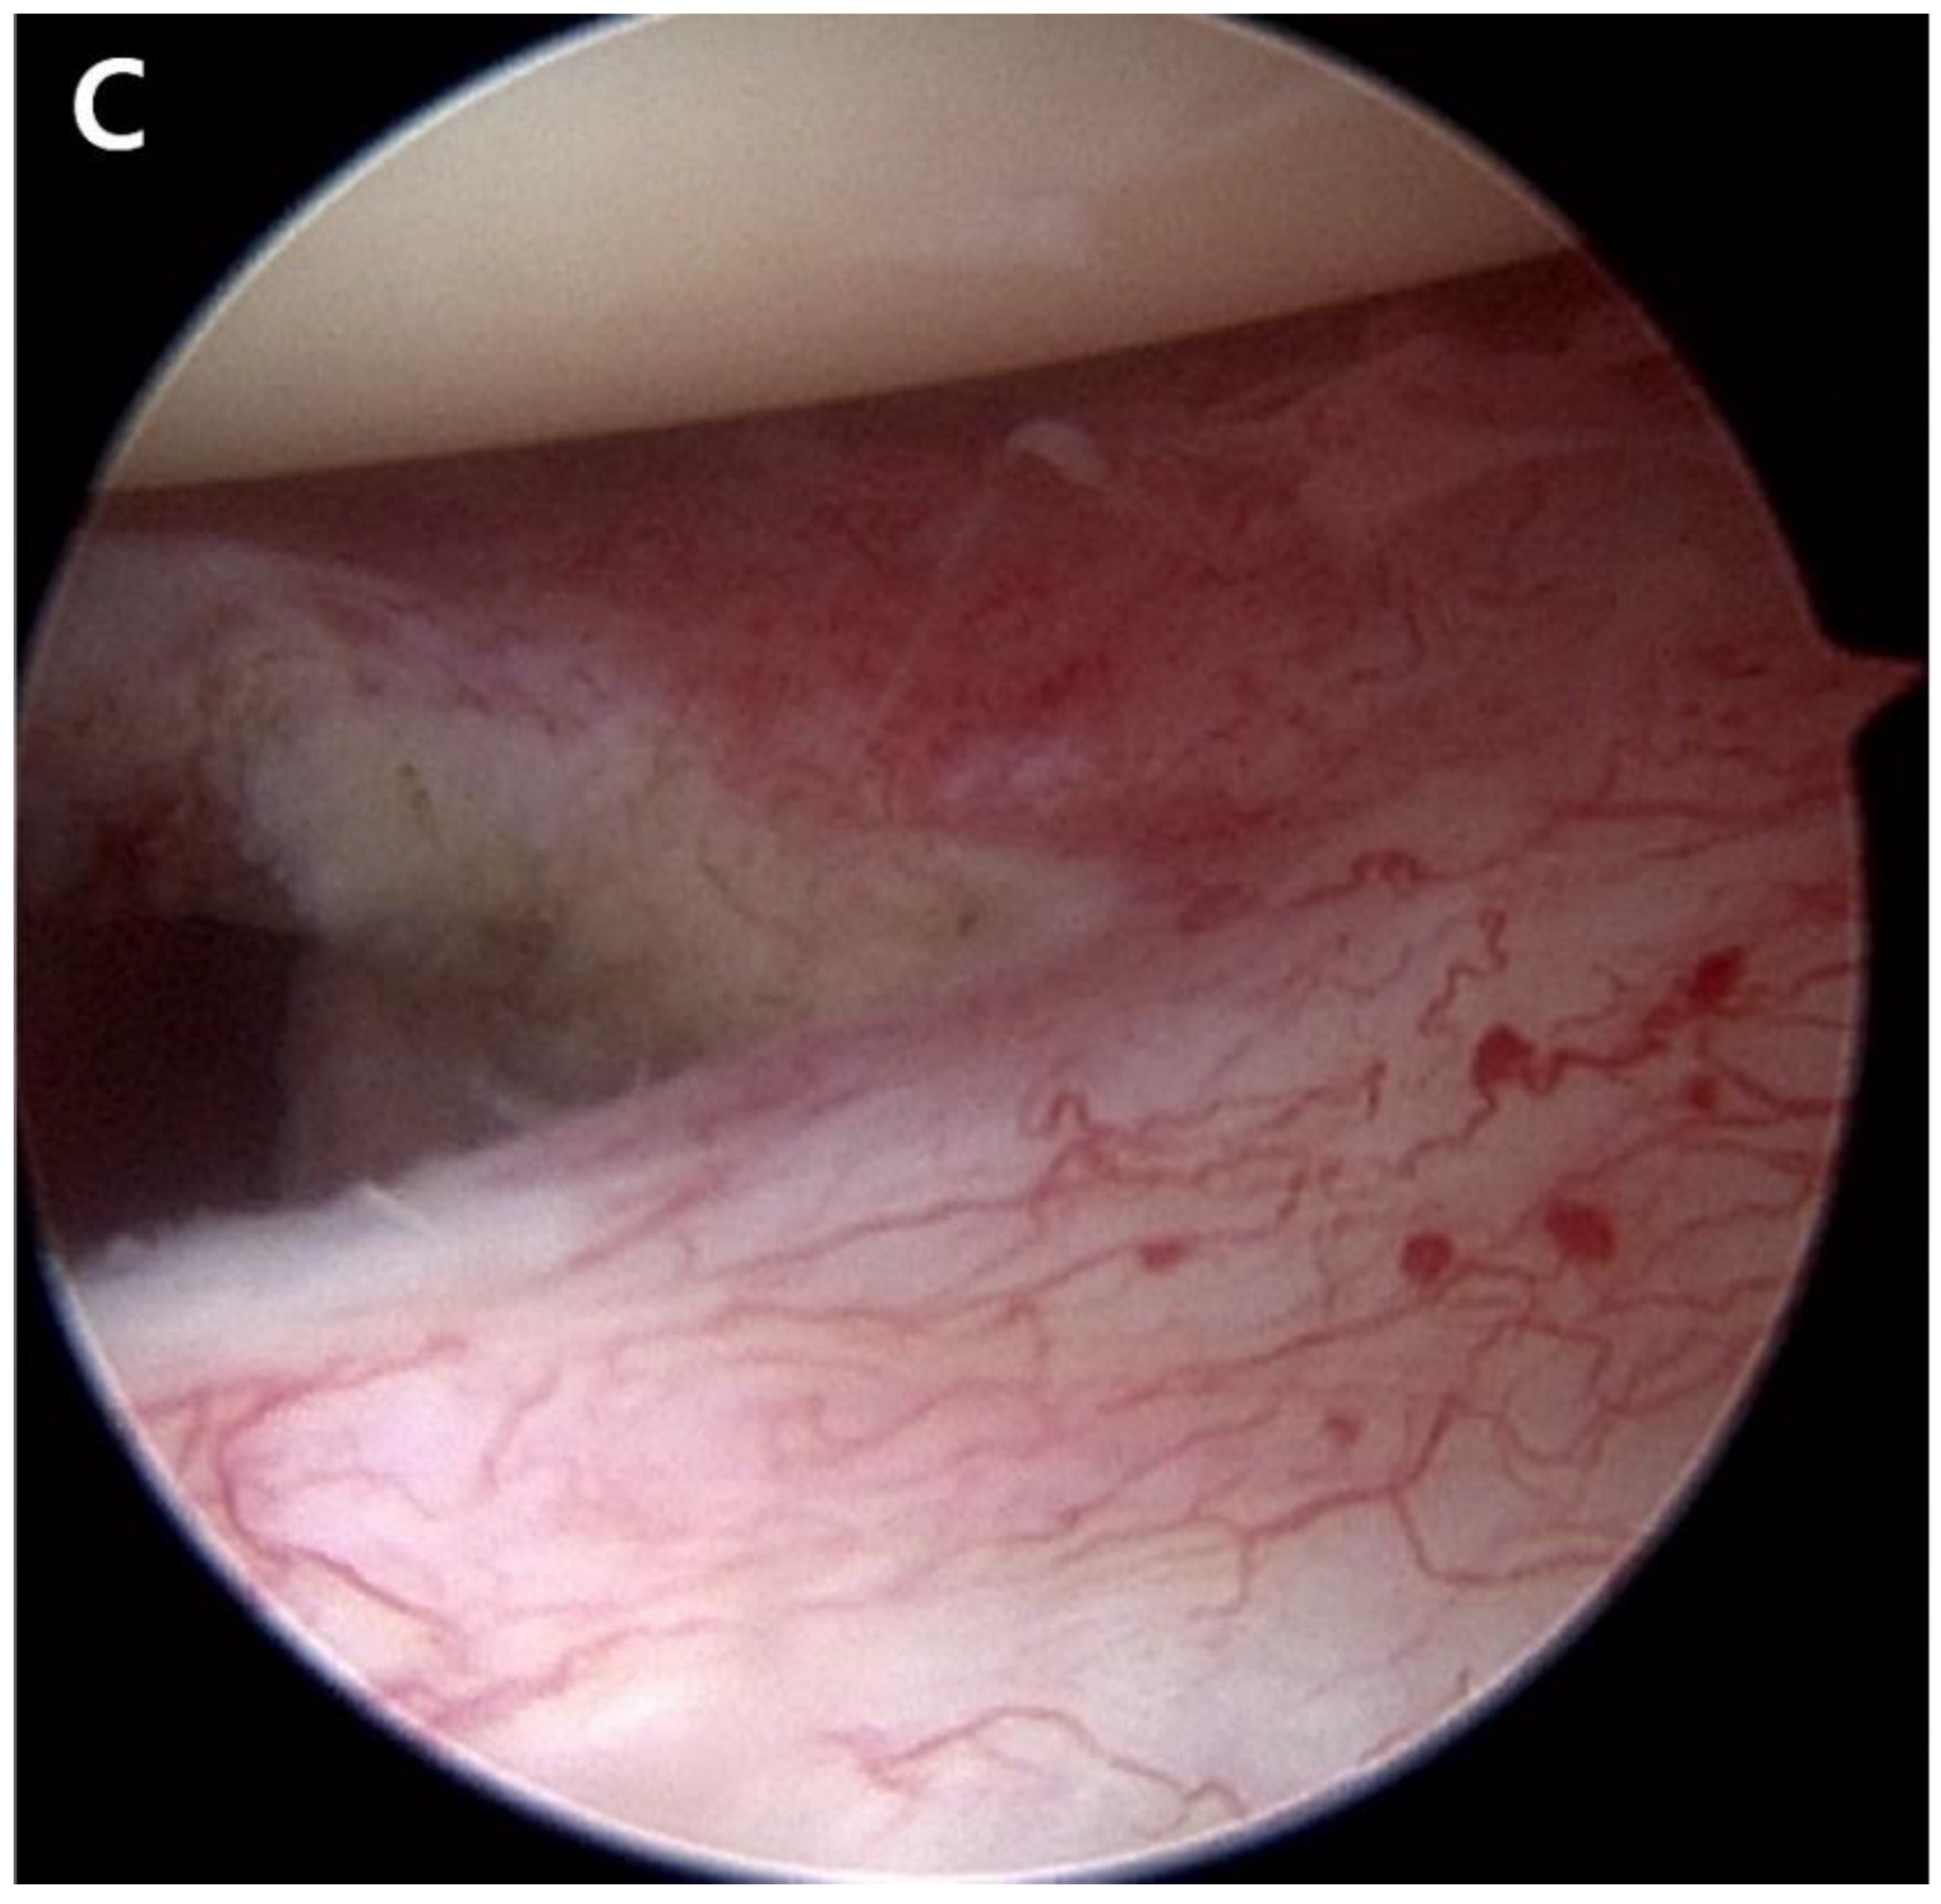

ACR was performed in the lateral decubitus position under general anesthesia. The fluid used during surgery was mixed with 1 mg of epinephrine per 3 L of normal saline, and the water pressure was maintained at 30–50 mmHg using an automatic infuser (10 K Fluid System, ConMed Linvatec, Largo, FL, USA). No abnormalities were observed in the rotator cuff, biceps long-head tendon, or glenohumeral joints on arthroscopic examination. ACR was performed according to the regular sequence, starting with the release of the rotator interval, middle glenohumeral ligament, and inferior and posterior capsules using a 3.0-mm 90° electrocautery device (Arthrocare, Smith & Nephew, Memphis, TN, USA) (Fig. 2). After ACR, the ROM under general anesthesia was defined as 150° forward flexion, 150° abduction, level of the 8th thoracic vertebral body for internal rotation, and 80° external rotation.

Figure 2. Arthroscopic capsular release was performed. A. Release of the thickened middle glenohumeral ligament was performed. B. The inferior capsule was released using a radiofrequency ablation device. C. Engorgement synovitis and capsule thickening were observed.